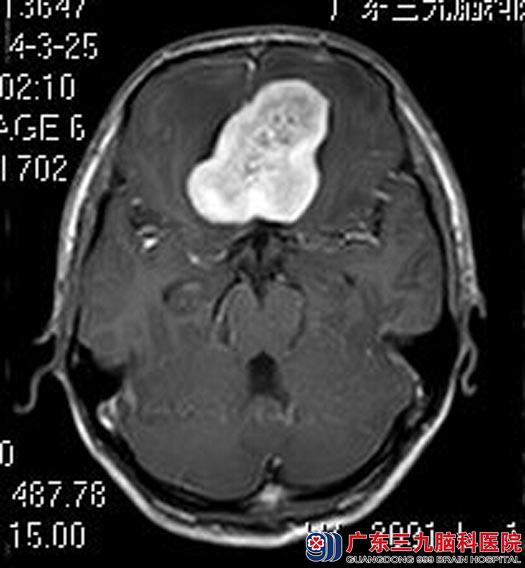

小郑回想起之前发生的那一幕仍感后怕。为求进一步诊治,他来到广东三九脑科医院,头颅MR检查提示前颅窝底示一团块状占位性病变,大小约37.6mm×38.5mm×38.7mm,考虑脑膜瘤。

综合神经外科鲁明主任主刀,在全麻下行前颅窝底脑膜瘤切除术,术中见肿瘤呈灰白色,位于前颅窝底,质中,血供较丰富,双侧视神经被肿瘤压迫向后下方,用超声刀、电磁刀分块切除肿瘤,显微镜下全切,双侧颈内动脉及其分支、双侧视神经保留完整。手术后,小郑顺利出院。术后病理结果:脑膜瘤。

手术前